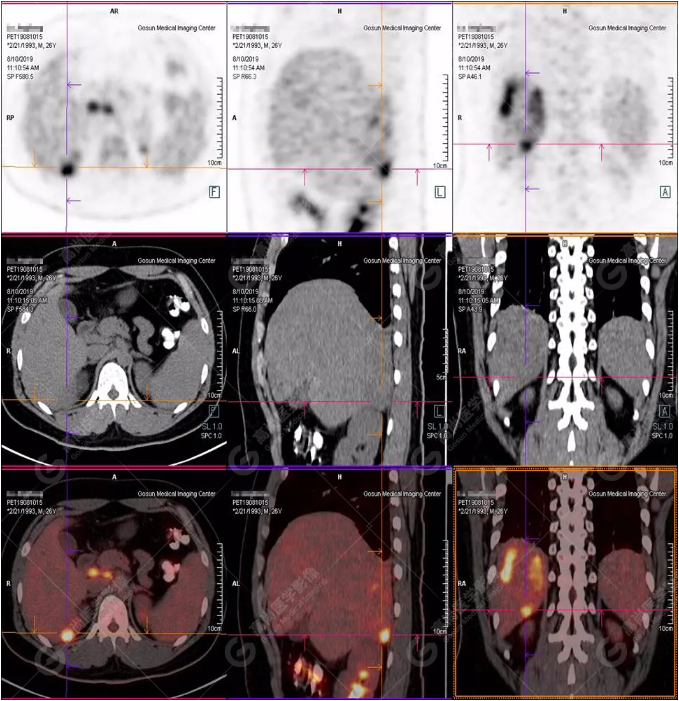

PET/CT全身圖

PET/CT診斷

嗜酸性粒細(xì)胞增多癥肝浸潤

5.嗜酸性粒細(xì)胞增多肝浸潤同白血病浸潤類似,主要表現(xiàn)多發(fā)性、結(jié)節(jié)性浸潤,伴肝大,單發(fā)浸潤少見